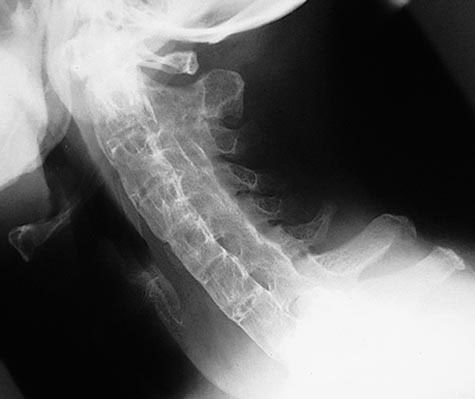

Diagnosis? Epidemiology? Orthopedic and Non-orthopedic manifestations?

Ankylosing Spondylitis

What does this patient have? What does your work-up include?